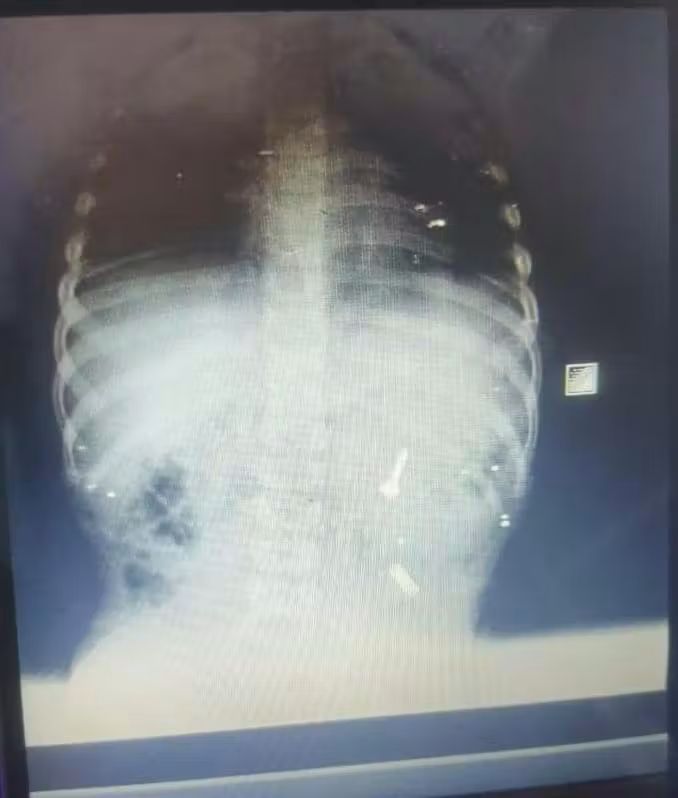

وبدأت الواقعة بوصول أسرة الطفل إلى قسم الطوارئ في حالة هلع شديد، وتم استقباله فورًا وإجراء أشعة عاجلة لتحديد موقع الجسم الغريب الذي استقر في أول أجزاء الأمعاء الدقيقة، وهو موضع يصعُب الوصول إليه بالمنظار لوجود تعرجات وزوايا ضيقة.

واصل الفريق الطبي محاولاته الدقيقة لإنقاذ الطفل دون اللجوء إلى جراحة مفتوحة قد تعرضه لمضاعفات خطيرة، وقرر التدخل الفوري بالمنظار ومنح فرصة لاستخراج المسمار قبل أن يؤدي إلى ثقب بالأمعاء، مما جعل التدخل محاطًا بتحديات كبيرة نظرًا لمكان الجسم الغريب وحجمه وطوله.

دخل الطفل غرفة العمليات فور وصوله، وتم استدعاء فريق طوارئ مناظير الجهاز الهضمي، حيث نجح الفريق—بمهارة ودقة—في الوصول إلى المسمار داخل الأمعاء واستخراجه كاملًا دون أي مضاعفات، وخرج الطفل من المستشفى بعد ساعات قليلة من العملية في حالة مستقرة وسط فرحة كبيرة من أسرته التي كانت تعيش لحظات قلق شديدة.